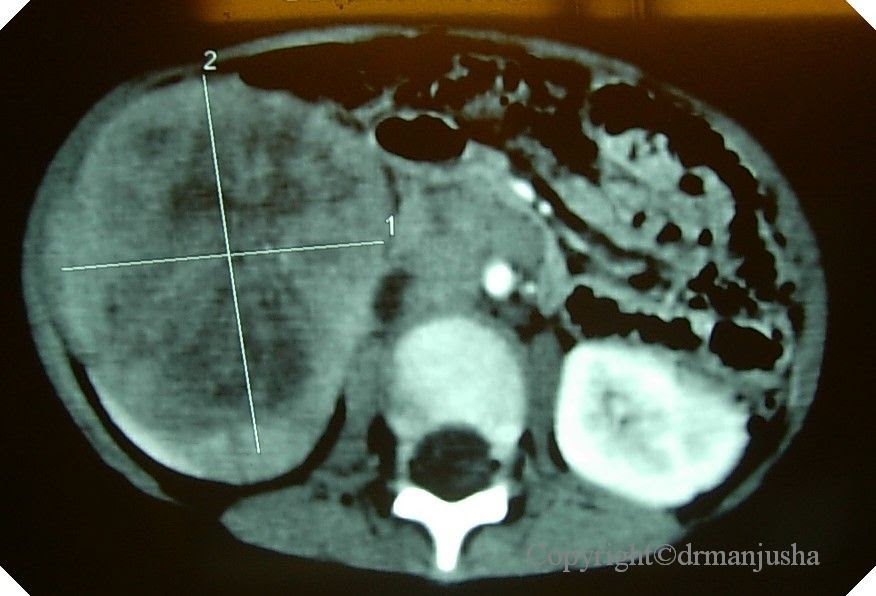

Диагностика и классификация нефробластомы у детей